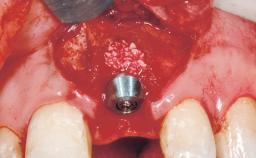

Bone Augmentation Horizontal|Simultaneous

Augmentation Materials Autogenous chips|Membrane

Socket Integrity Sufficient, with intact bone walls

Bone Volume Sufficient, with intact walls